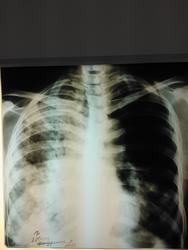

Женщина пенсионного возраста поступила в отделение сестринского ухода при терапии с диагнозом "Алкогольная интоксикация", жалоб особых нет, раннее не обследована, из анамнеза злоупотребление алкоголем. после проф. флюшки отправлена на консультацию к онкологу и фтизиатру. фтизиатр свое исключает и также отправляет к онкологу, онколог рекомендует КТ ОГК, на КТ врят ли поедет так как из глухой деревни, в анализах крови ничего особенного, хотеллось бы узнать мнения коллег по данному случаю.

Любой рентгенлаборант способен, при синдроме затемнения в легком, построить дифряд: пневмония? туберкулез? рак?

По-моему это типичная картина активного туберкулеза - инфильтраты со склонностью к слиянию, очаги с нечеткими контурами.. Средостение смещено вправо, что может указывать на фиброз в правом легком.. Спокойные анализы, неяркая клиника туда же - к туберкулезу. На каком основании фтизиатр так быстро сказал, что это не его?

А где же центральный рак на боковом снимке? Все те же инфильтраты, опухолевой массы не видно.. Тем более по-моему начинается обсеменение нижних отделов левого легкого.. Неужели больше нет сторонников тбц. Если на КТ не доедет, то пусть хоть мокроту как следует соберут посмотрят

В верхней доле слева не прослеживается легочной рисунок... Возникла мысль о пневмотораксе, не исключая вышесказанные диагнозы...

Формально по рентгенограммам, особенно прямой, в первую очередь, на мой взгляд, можно подумать о гангрене правого лёгкого. Правда такой диагноз у многих вызывает неприятие.

сегодня пациентке провели контрольную R-графию (снимок только в прямой проекции и на другом аппарате - немного "мягче", предыдущий сломался, а этот боковой не смог снять), сравнить тяжело (на разных аппаратах, разная экспозиция и тд и тп) но по мне динамика отрицательная.